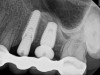

The augmentation was accessed through a crestal approach in both site Nos. 13 and 14 using a crestal approach kit (Integrated Dental Systems, www.megagenids.com). The sinus express bur was set using a built-in stopper 1 mm past the radiographic sinus floor. After the use of several hand instruments, the Schneiderian membrane was lifted, and an intact sinus membrane was observed. The osteotomies were connected through the sinus floor (Figure 9). The bone graft was placed into the sinus cavity and two implants (Integrated Dental Systems) were placed and buried (Figure 10). Four months later the implants were second-staged and the soft tissue was apically repositioned (Figure 11). The final impression was taken 2 weeks later and 10 days after that, the final crown was delivered (Figure 12).

Figure 10. Two implants placed into the osteotomies of site Nos. 12 and 13.

Figure 10